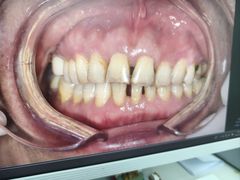

• 牙博士口腔品牌连锁(杨浦店)

• -牙博士口腔品牌连锁(杨浦店)

Angela | 25-03-28